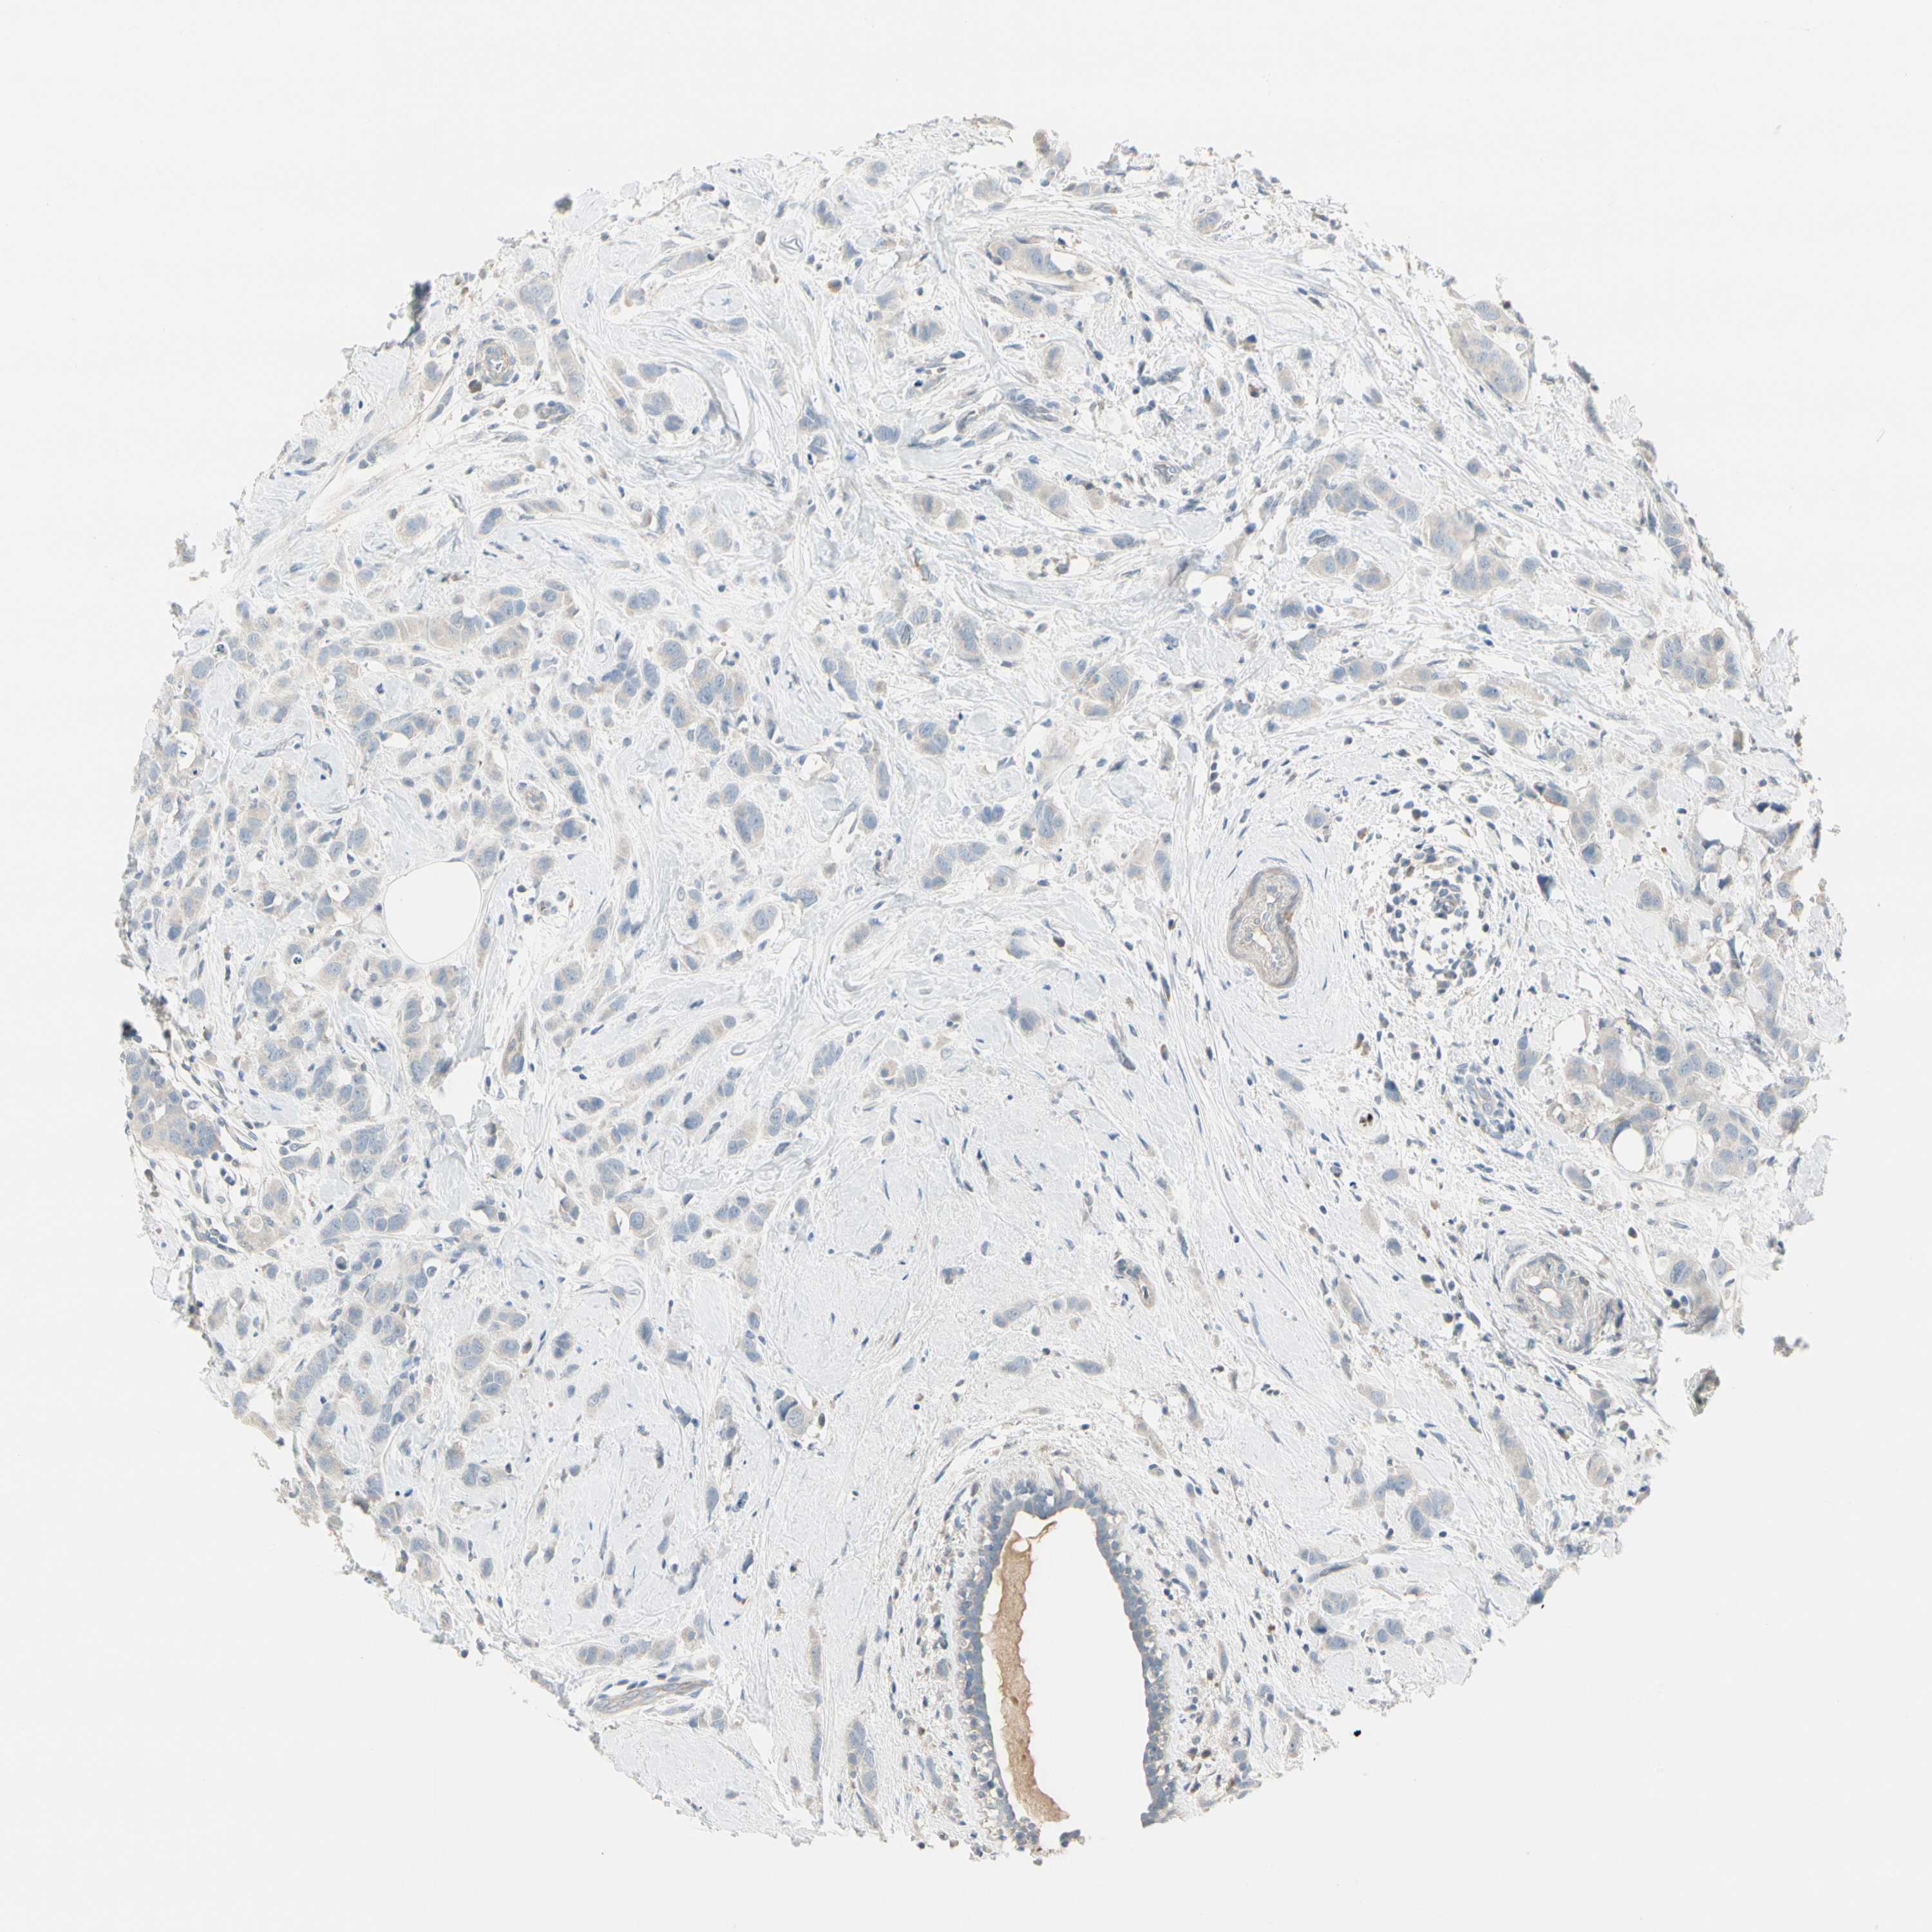

BRCA TCGA BRCA VALIDATION PROTEIN EXPRESSION

ANTIBODIES

AND

VALIDATION